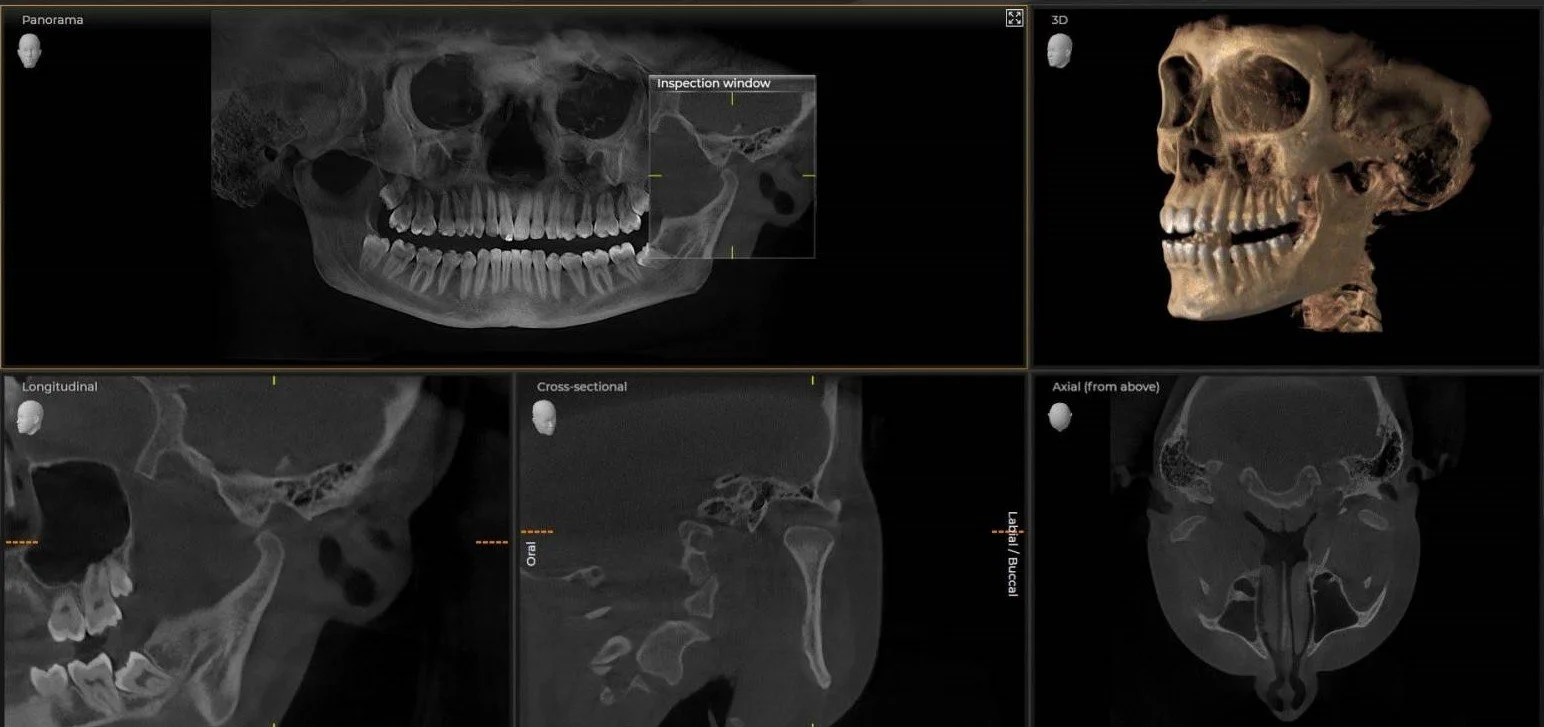

3D CBCT scan at New Standard Imaging in Birmingham, AL

Using advanced Cone Beam CT (CBCT) machines and high accuracy intraoral scanners, we provide unrivaled x-ray and digital impression images that can be used to better diagnose and treat patients.

• Determine whether a tooth should be treated or extracted.

• Place implants confidently knowing the true bone width and lingual contours.

• Determine if an impaction is resting against a neighboring tooth or if there is a secondary nerve canal.

• Examine the position and mobility of the condyles.

• See the upper airway and nasal passages with our largest field of view.